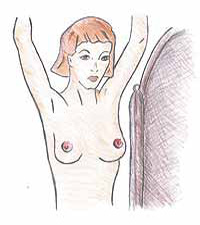

2. Εξέτασε το μαστό σου μπροστά στον καθρέφτη Εξέτασε οπτικά τους μαστούς σου με τα χέρια στη μέση. Στη συνέχεια ανέβασε τα χέρια πάνω από το κεφάλι. Ψάξε για οποιaδήποτε αλλαγή στο σχήμα των μαστών σου, για πρηξίματα ή για τέντωμα του δέρματος όπως επίσης και για οποιεσδήποτε αλλαγές στις θηλές. Συνέχεια τοποθέτησε τα χέρια στους γοφούς και σπρώξε προς τα κάτω ώστε να τεντώσει το δέρμα, να τεντώσουν οι μυς του μαστού. Υπάρχουν λίγες γυναίκες οι οποίες έχουν δύο ίδιους μαστούς.

Εξέτασε οπτικά τους μαστούς σου με τα χέρια στη μέση. Στη συνέχεια ανέβασε τα χέρια πάνω από το κεφάλι. Ψάξε για οποιaδήποτε αλλαγή στο σχήμα των μαστών σου, για πρηξίματα ή για τέντωμα του δέρματος όπως επίσης και για οποιεσδήποτε αλλαγές στις θηλές. Συνέχεια τοποθέτησε τα χέρια στους γοφούς και σπρώξε προς τα κάτω ώστε να τεντώσει το δέρμα, να τεντώσουν οι μυς του μαστού. Υπάρχουν λίγες γυναίκες οι οποίες έχουν δύο ίδιους μαστούς.